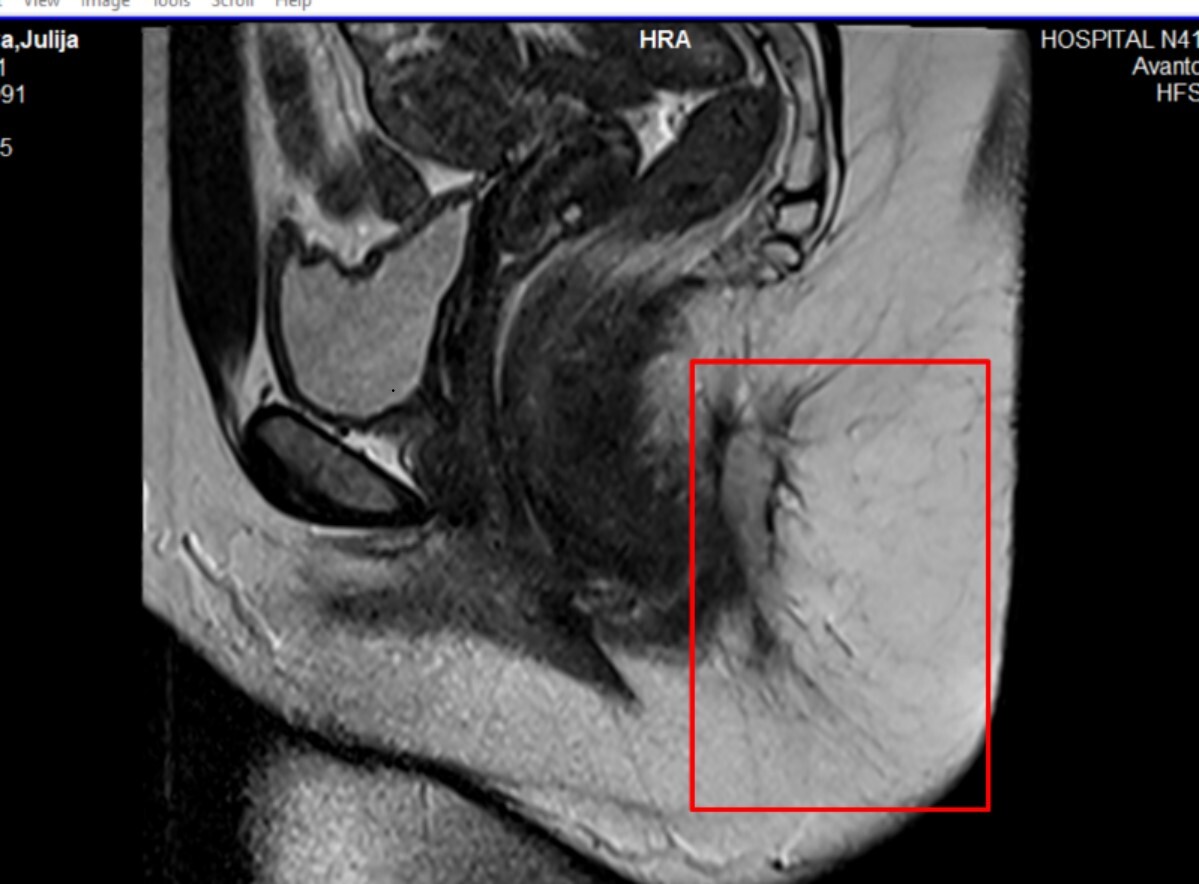

Сделала МРТ - а там капец